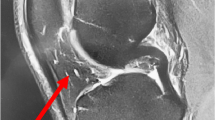

IPFP tissue contained large areas of fat-rich adipocytes permeated by a vascular bed of arterioles, venules, and capillaries, which were easily identified in the histological sections. The antibody recognising vascular pericytes, 3G5, predominantly stained cells in the tunica adventitia, which formed the supporting layer of the arterioles (Figure 1a,b), whereas anti-vWF (endothelial cell marker) stained endothelial cells in the tunica intima (Figure 1c,d) and anti-αSMA (smooth muscle cell marker) stained cells in the tunica media, forming the muscular wall of the arteriole (Figure 1e,f). All three antibodies were therefore localised to cells in different regions of the small arterioles. The positive staining for 3G5 in the perivascular cells suggested the presence of pericytes in the IPFP tissue.

3G5, von Willebrand factor (vWF), and alpha smooth muscle actin (αSMA) staining in the infrapatellar fat pad (IPFP) tissue vasculature. 3G5 (a, b) staining predominantly the tunica adventitia consisting of supporting tissue in the vasculature, vWF (c, d) staining predominantly the tunica intima consisting of the endothelial layer and the basement membrane, and αSMA (e, f) staining predominantly the tunica media consisting of the muscular layer of the arteriole are shown at × 10 (left panels) and × 40 (right panels) magnifications in the IPFP tissue.

Evidence for pericytes in the IPFP tissue and IPFP-derived cells